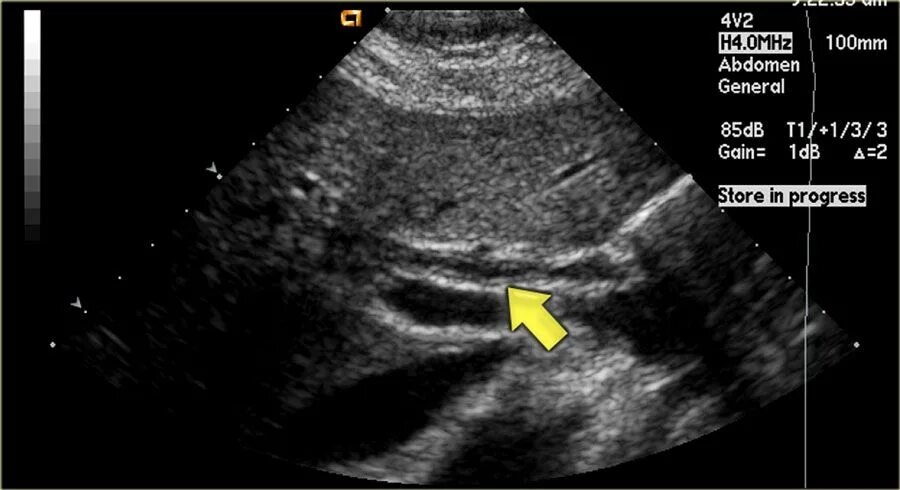

Узи шип